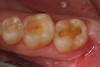

Fig 9. A preoperative occlusal view of teeth Nos. 18 and 19 with composite restorations that are exhibiting marginal breakdown.

Figure 9

Fig 10. After removal of the existing restorations and associated recurrent decay, both cavities are very deep and there is a pinpoint pulpal exposure on tooth No. 19.

Figure 10